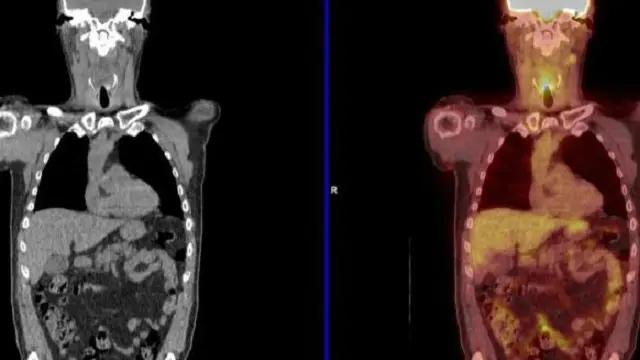

وتستخدم تقنية تصوير مقطعي بالإصدار البوزيتروني (PET-CT) صبغة ذات إشعاع نشط خلال المسح المقطعي، والتي تحدد الخلايا السرطانية التي تنقسم بسرعة.

وذلك يسمح للأطباء برؤية ما إذا كانت هناك خلايا سرطانية مازالت حية في الرأس أو الرقبة.

وقال البروفيسور هشام مهنى، من جامعة برمنجهام، لبي بي سي نيوز: "إن الخلايا السرطانية تختفي بين الخلايا الميتة، وباستخدام PET-CT يمكن معرفة ما إذا كانت مازالت حية أم لا."